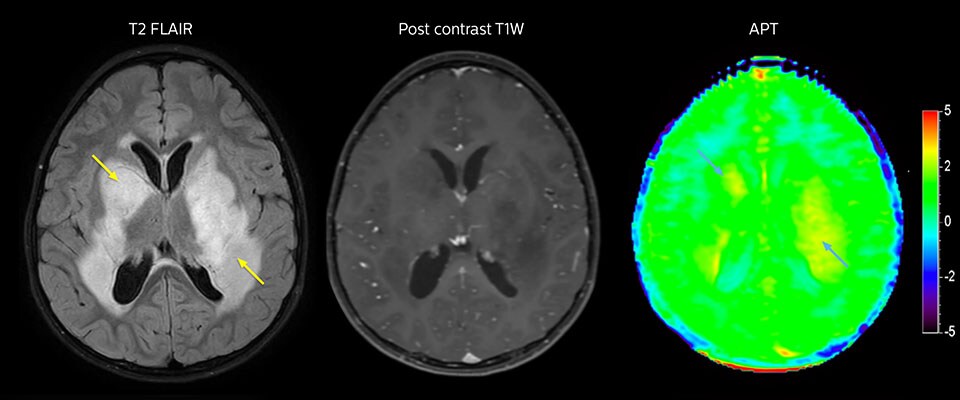

MRI may be performed after tumor resection, to look for residual tumor or tumor regrowth. Also here, the different contrast mechanism of APT may help in diagnosis. Dr. Miller remembers a particular case. “After a very good resection, we saw small changes on the postcontrast T1-weighted and the T2-weighted images that looked like a post-surgical little bit of fluid. Interestingly, however, we saw a focal area of APT signal, right in the center of that abnormality. As we usually do when a bit unsure, we followed it up and, unfortunately, found tumor regrowth in that region,” Dr. Miller says. “Cases like this motivate me, and others who care about this population, to investigate how this APT method could be used on large scale in this population and help us in providing high value diagnostic information.” The hospital’s physicians also saw a case where APT had a negative predictive value. Following the resection of a highgrade tumor, they saw a similar small change in the images of this patient. However in this case, the APT signal was rather low. In a recent rescanning of this patient, no recurrence was seen.

MRI with APT post resection

Immediately post resection MRI was again performed. T2-weighted and postcontrast T1-weighted images are quite inconclusive for distinguishing residual tumor tissue from postoperative tissue changes. On the APT image some high signal is still seen, which would suggest residual tumor tissue.

Follow-up over time

In later follow-up scans the post-contrast T1-weighted images suggest recurrent tumor growth. So, it would be interesting to study the predictive value of APT in a large patient group.